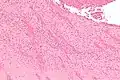

صورة مجهرية ذات تكبير متوسط تُظهر عملية التصفيح (تكوّن الطبقات) في حالة انصمام رئوي مميتة. (صبغة الهيماتوكسيلين والأيوزين).

انْصِمامٌ خُثارِيّ رئوي حديث تُرى فيه خطوط زان ظاهرة بوضوح. المناطق ذات اللون الفاتح تتكون من الفايبرين والصفائح الدموية ، أما المناطق ذات اللون الأحمر فهى كريات الدم الحمراء.